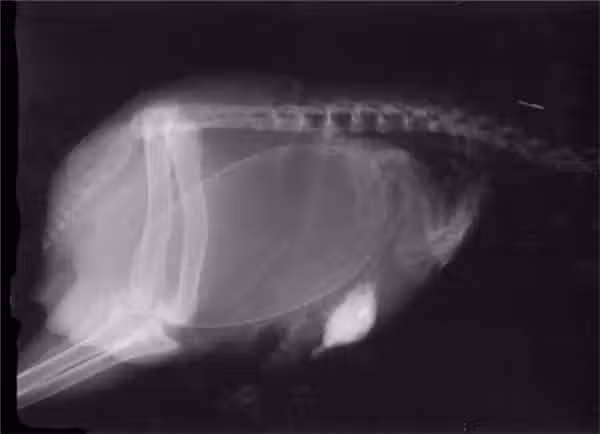

14.科摩多巨蜥